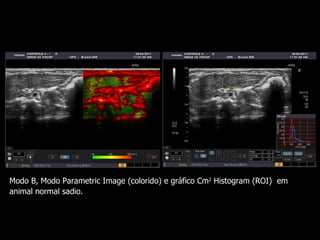

Modo B,  Modo Parametric Image (colorido) e gráfico Cm 2  Histogram . Neste exemplo, observa-se imagem no modo parametric image, áreas de fibrose (em vermelho e amarelo), que refletem a curva em azul no modo Cm histogram, de aspecto irregular, compatível com fibrose.